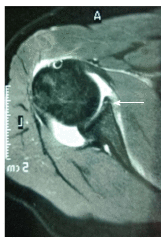

Figures